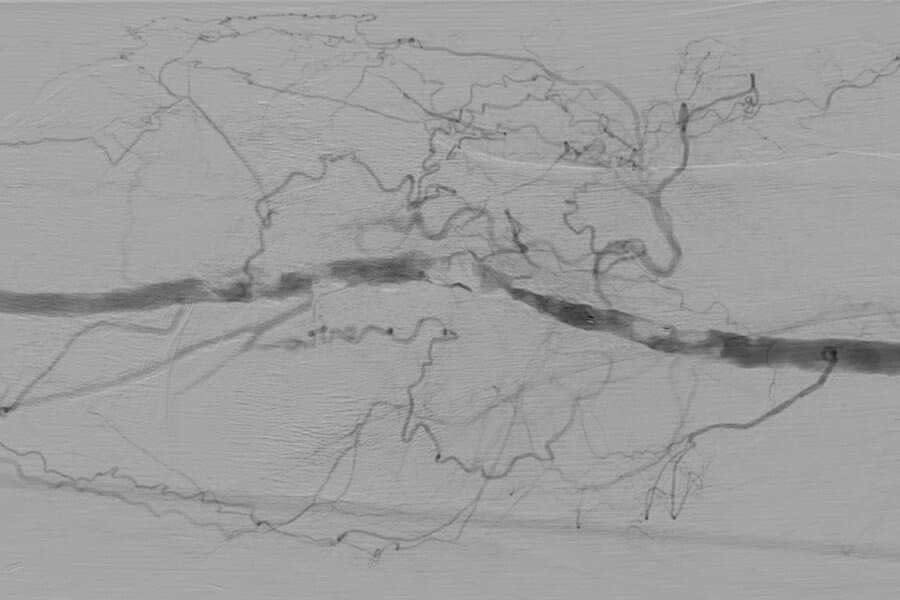

Das Institut für Diagnostische und Interventionelle Radiologie am SK Vöcklabruck hat das Behandlungskonzept für PatientInnen mit pAVK nun erweitert: Mit der Intravaskulären Lithotripsie (IVL) und der Rotationsthrombektomie können zwei innovative Therapieformen minimal-invasiv und praktisch schmerzfrei angeboten werden.